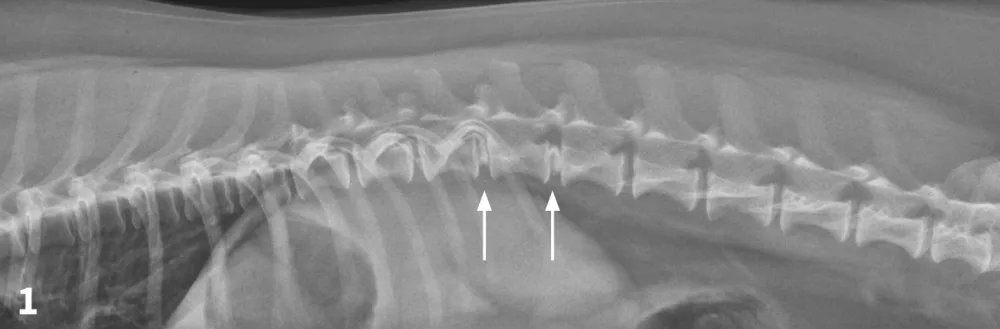

Figure 1

Lateral spinal radiograph. Mineralization and narrowing of the T13-L1 and L1-L2 disc spaces was noted (arrows).

The veterinarian administered 0.02 mg/kg acepromazine IM and 1 mg/kg morphine IM1 and obtained lateral and VD views of the TL vertebral column. (See Figures 1 & 2.) The radiographs showed no evidence of lytic change but did show mineralization and narrowing of the T13-L1 and L1-2 intervertebral disc spaces (arrows).